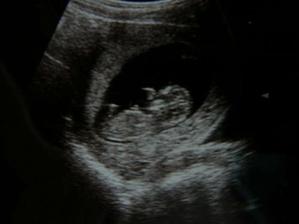

Nas maly anjelik